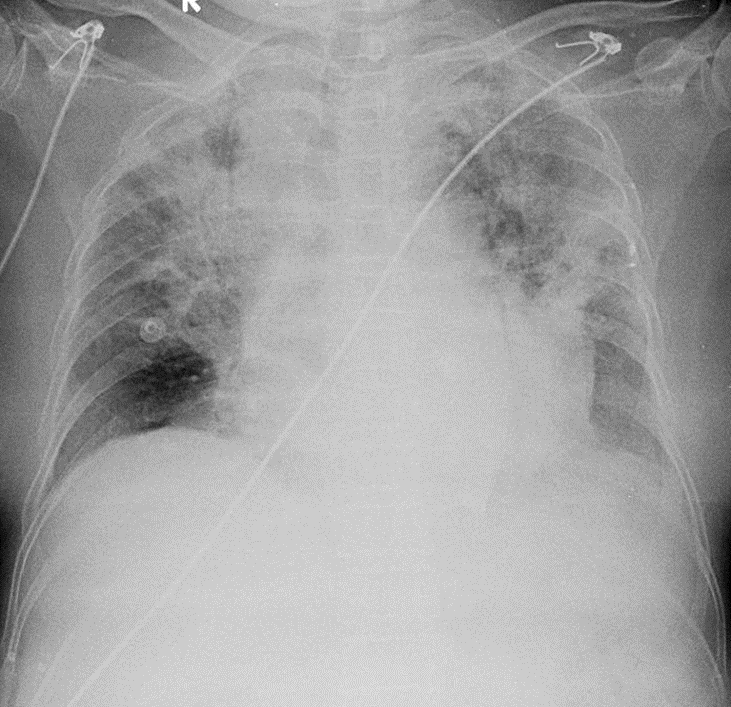

Hãy phân tích tình huống nữ 76 tuổi

1-Thâm nhiểm phế nang lan tỏa hai phổi => Viêm phổi 2-Tim to 3-Cản quang điện cực thành ngực hai bên